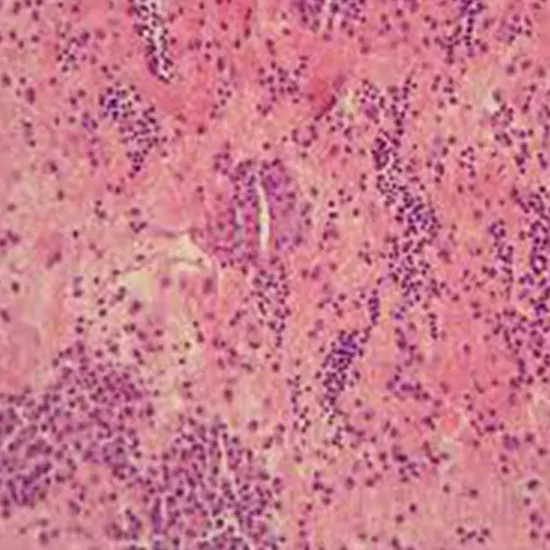

Only if subsequent peritonitis is a worry should ascitic fluid gramme stain be ordered due to its low yield. Instead, a diagnosis can be made using the cell count and differential. The best chance to identify the infectious organism is with prompt fluid injections into blood culture flasks at the patient's bedside.